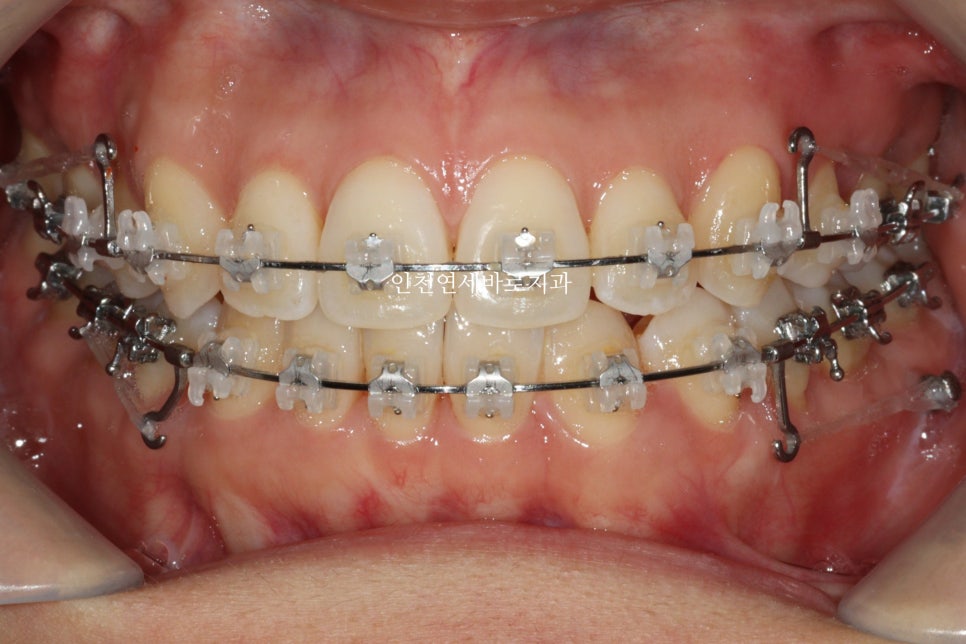

원하시는 대로 클리피씨를 붙이기로 했고 ㅠ

일반 장치로 진행을 이어갔습니다. 저로서는 너무 아쉬움

그래도 일단 목표한대로 끝내야하니 계속 치료를 이어갑니다

아마도 조금만 더 참고 꼈다면 인비절라인으로 잘 마무리 할 수 있지 않았을까 ㅠ